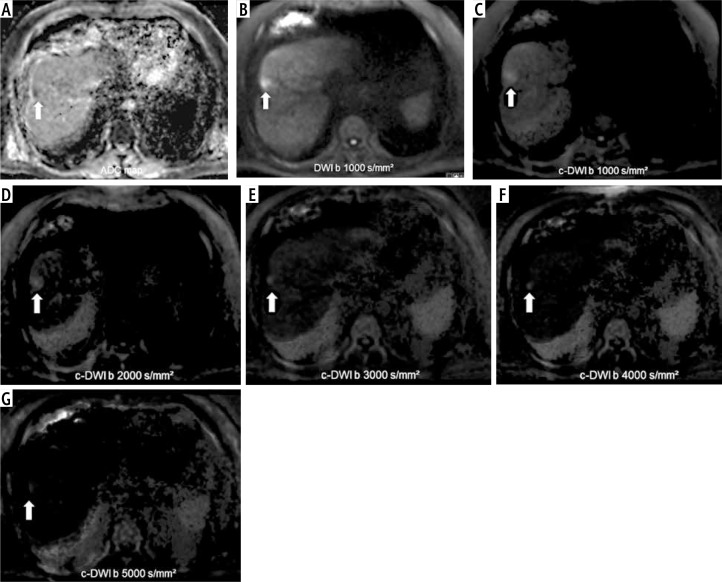

Material and methods: In total, 37 patients with histopathologically confirmed HCC were retrospectively ana-lyzed. DWI was acquired with b-values of 50, 400, and 800 or 1000 s/mm² on a 1.5 T magnetic resonance imaging (MRI) scanner. The c-DWI was calculated using a monoexponential model with high b-values of 1000, 2000, 3000, 4000, and 5000 s/mm². All high b-value c-DWI images were compared to the standard DWI in terms of volume, detectability of hepatic lesions, and image quality.

Results: Regarding lesion volume and image quality there were no statistically significant differences between standard and c-DWI. HCC lesions measured on DWI images were statistically significantly larger compared to c-DWI images starting from a b value of 2000 s/mm2 (DWI vs. c-DWI b 2000 s/mm2: 2 cm3 [1-12] cm3 vs. 1 cm3 [0-17] cm3, p < 0.05). Moreover, there was deterioration of image quality starting at b = 2000 s/mm2. There were no significant differences in terms of lesion signal intensity in DWI and c-DWI images. There were no differences for the DWI parameters according to MVI status.

Conclusions: C-DWI images with high b-values up to b = 1000 s/mm2 demonstrate comparable detectability of HCC compared to standard DWI. The investigated DWI parameters were not associated with MVI status. Further research is needed to evaluate the potential benefit of high b-value c-DWI.